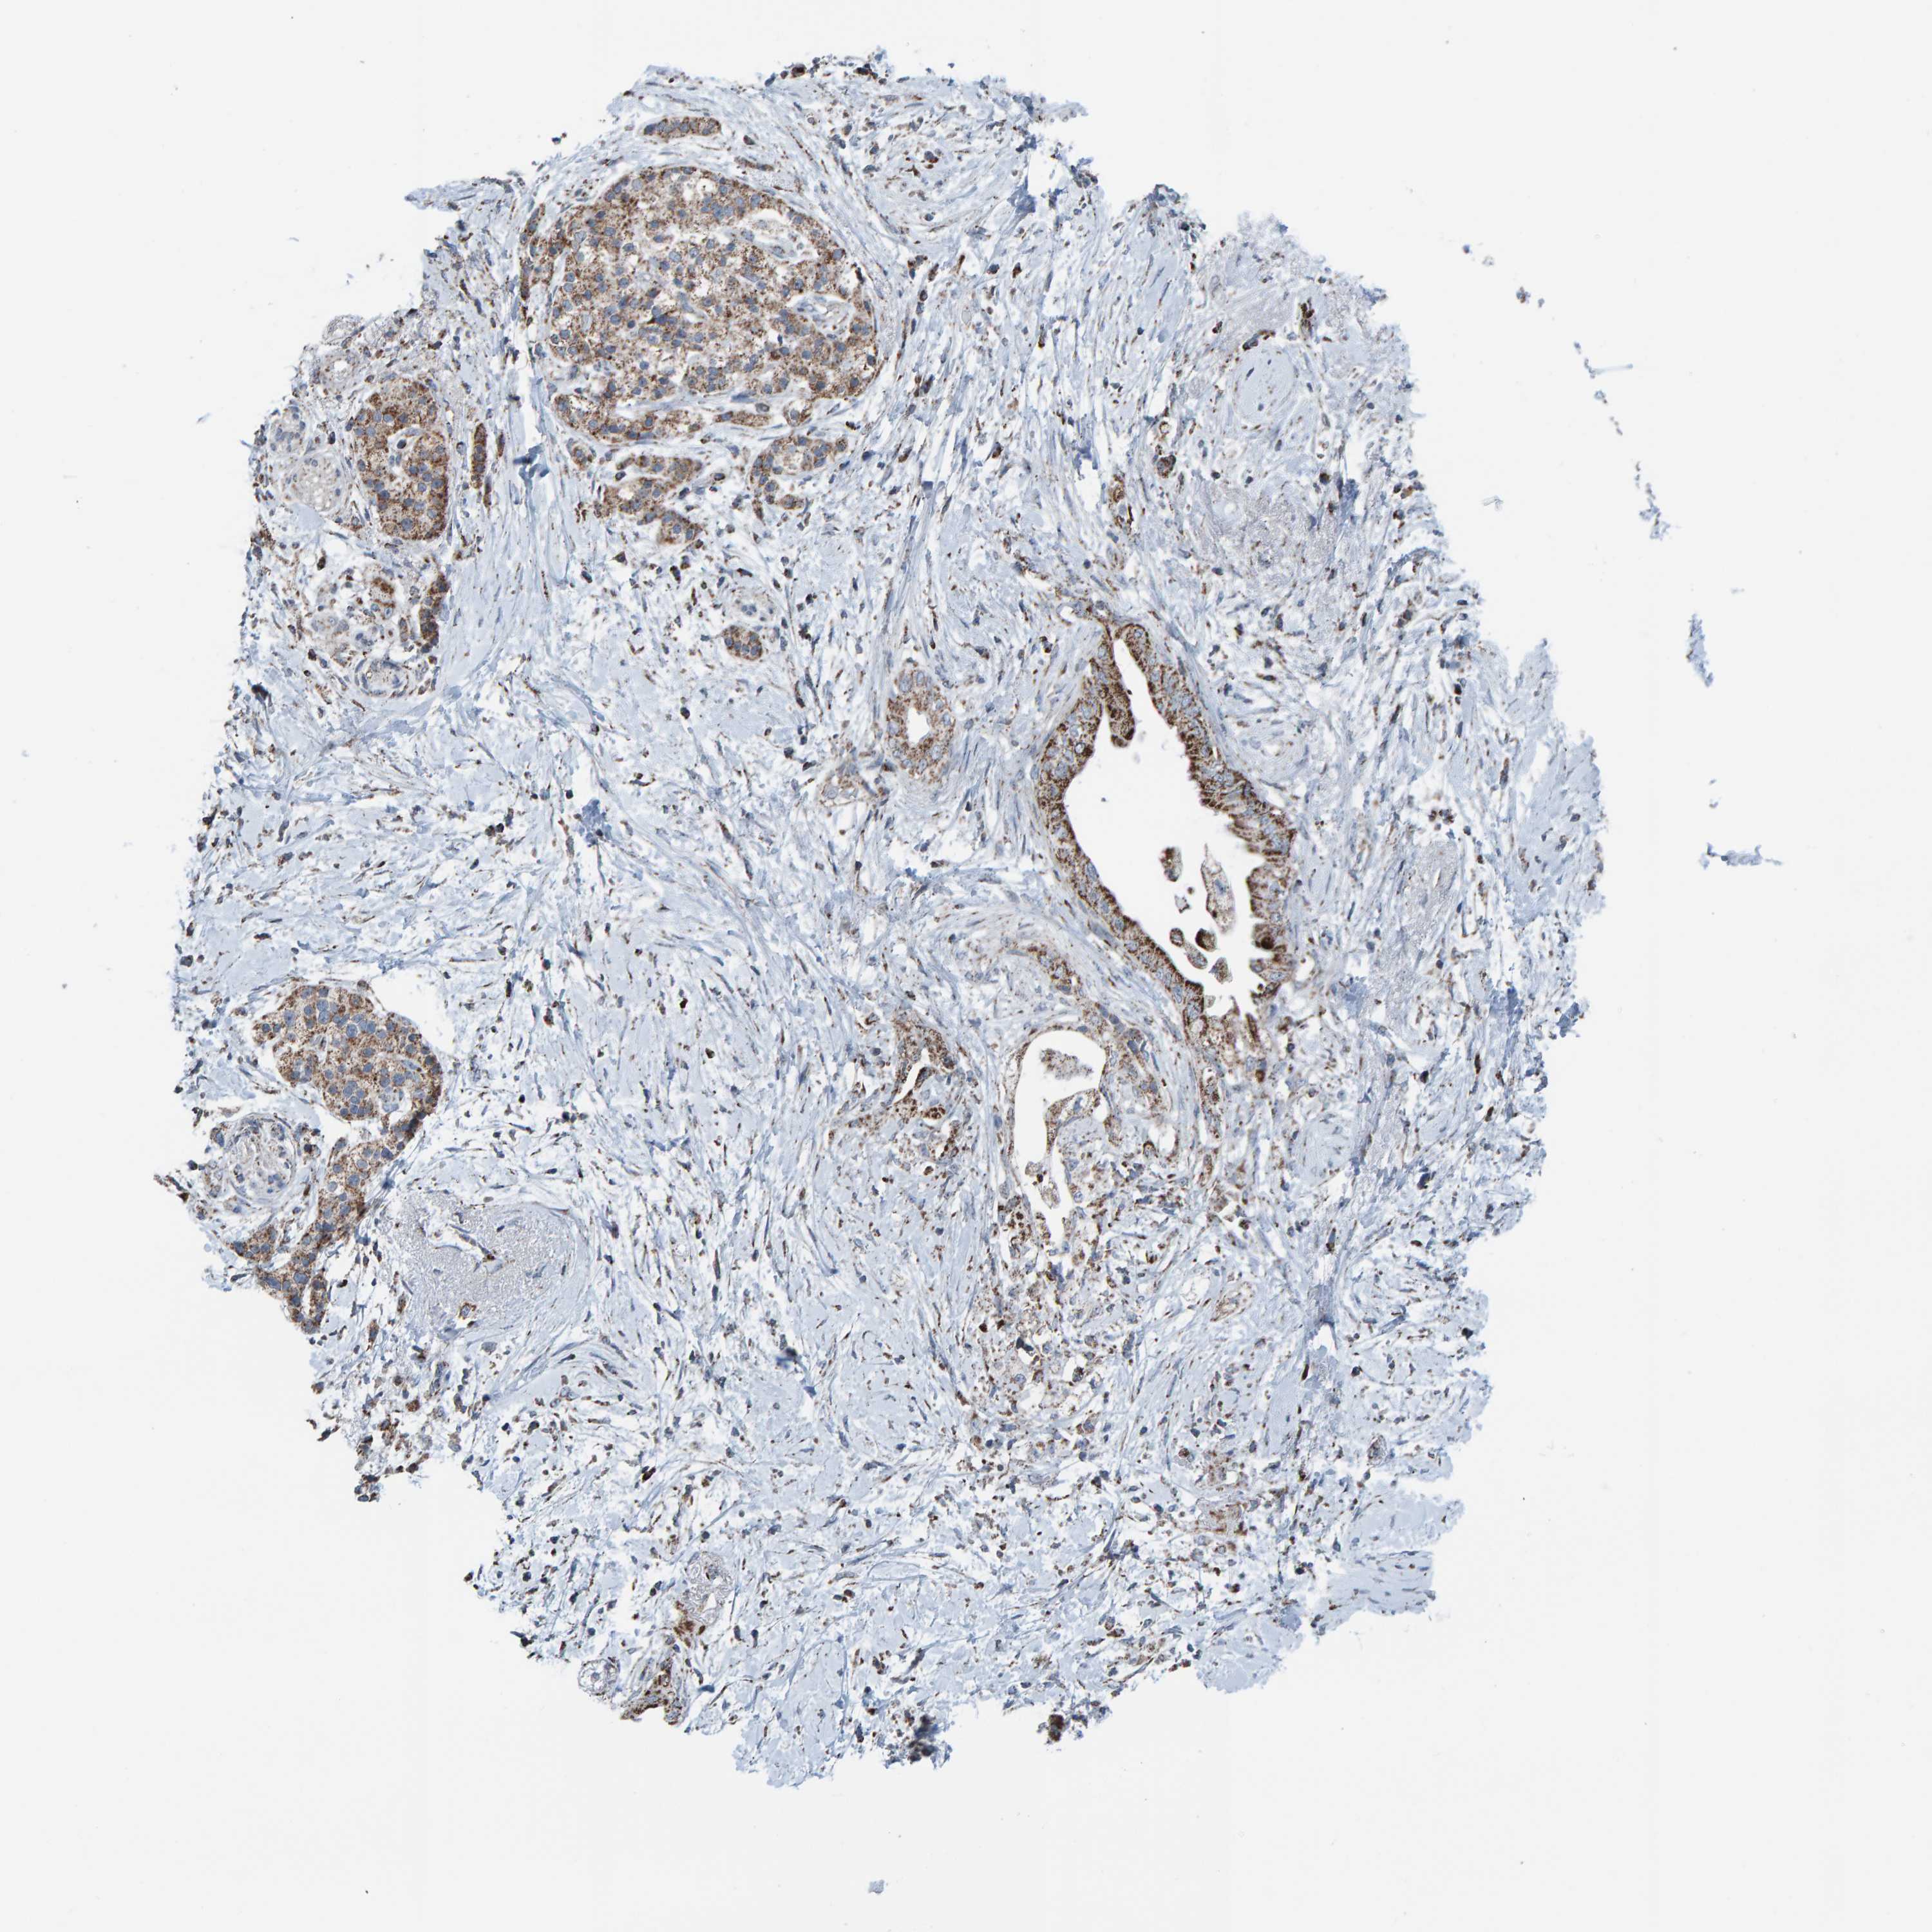

PANCREATIC CANCER - Protein expressioni

A mouse-over function shows sample information and annotation data. Click on an image to view it in a full screen mode. Samples can be filtered based on level of antibody staining by selecting one or several of the following categories: high, medium, low and not detected. The assay and annotation is described here.

Note that samples used for immunohistochemistry by the Human Protein Atlas do not correspond to samples in the TCGA dataset.

Antibody stainingi

Antibody staining in the annotated cell types in the current human tissue is reported as not detected, low, medium, or high, based on conventional immunohistochemistry profiling in selected tissues. This score is based on the combination of the staining intensity and fraction of stained cells.

Each image is clickable and will lead to virtual microscopy that enables deeper exploration of all samples and also displays staining intensity scores, fraction scores and subcellular localization as well as patient and tissue information for each sample.

Antibody HPA023806

Staining

High

Medium

Low

Not detected

Intensity

Strong

Moderate

Weak

Negative

Quantity

>75%

75%-25%

<25%

None

Location

Nuclear

Cytoplasmic/membranous

Cytoplasmic/membranous,nuclear

Adenocarcinoma, NOS